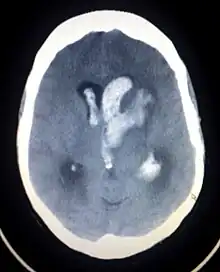

Axial CT scan of a spontaneous intracranial hemorrhage

Intracranial hemorrhage (ICH), also known as intracranial bleed, is bleeding within the skull.[1] Subtypes are intracerebral bleeds (intraventricular bleeds and intraparenchymal bleeds), subarachnoid bleeds, epidural bleeds, and subdural bleeds.[2]